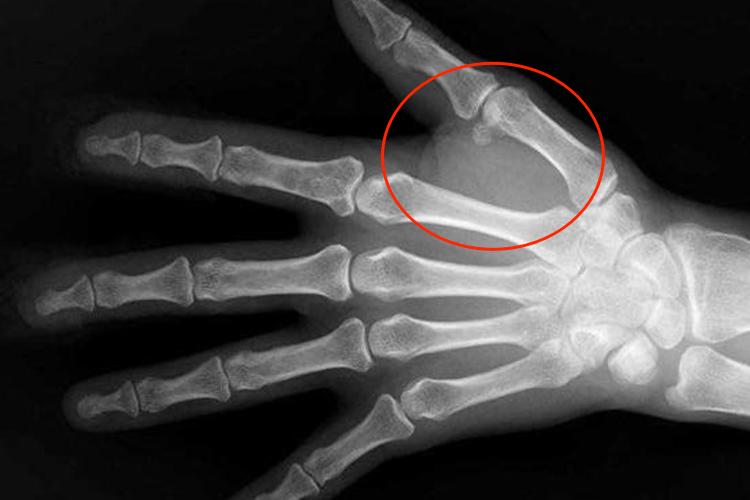

软骨瘤

发生于指(趾)骨的软骨瘤,通常位于骨中央。软骨瘤X线征象表现为边缘清晰、整齐的椭圆形囊状透明阴影,呈膨胀性生长,受累骨皮质因膨胀变薄,周围会有一薄层增生硬化现象,在透明的肿瘤阴影内,可见散在的砂粒样钙化点,有些表现为模糊的烟圈样钙化,这是主要X线特征。

发生于长骨中的单发性内生软骨瘤者,肿瘤阴影较大,通常偏于一端,表现为溶骨性的病变,其内可见钙化阴影,骨皮质的膨胀显著,常呈分叶状侵蚀,但是没有骨膜反应。